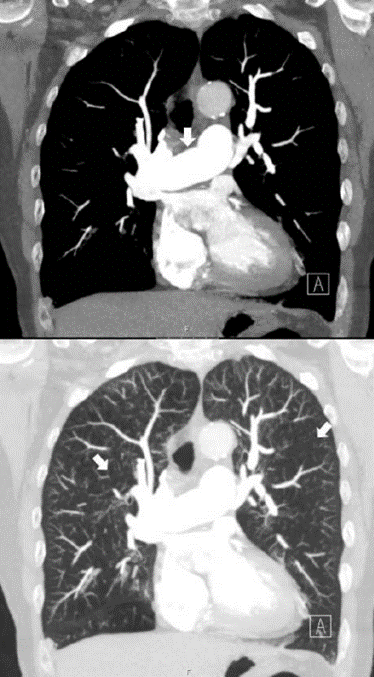

DT lunga

Vad visar bilden?

Små nodulära förändringar, kring pleuran, men också runt kärl liksom mellan lober, mellan bronker typiskt vid sarkoidos, även amyloidos som differentialdiagnos, liksom tuberkulos.